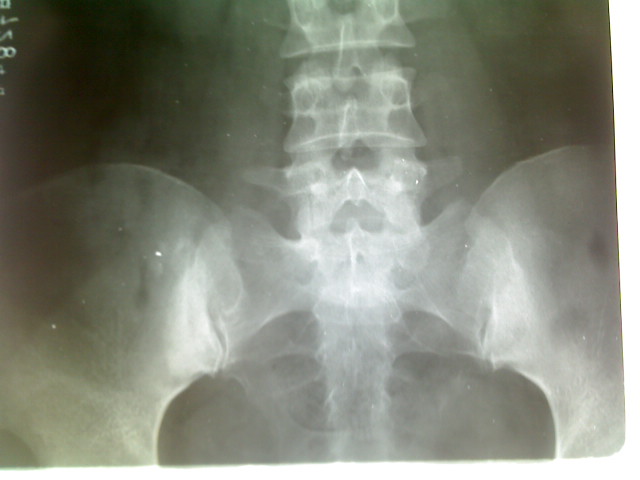

标题: X5229:双侧髂骨致密性骨炎 [打印本页]

好。三角形、不跨关节、典型的。谢谢分享!

本病多见于青年女性,主要表现为慢性腰骶部疼痛和发僵,临床检查除腰部肌肉紧张外无其他异常,诊断主要靠x线后前位平片,典型表现髂骨延骶髂关节之中下三分之二部位有明显的骨硬化区。呈三角行向上,密度均匀,不侵犯骶髂关节面,无关节狭窄或糜烂。要注意和强直性脊柱炎鉴别或排除强直性脊柱炎。